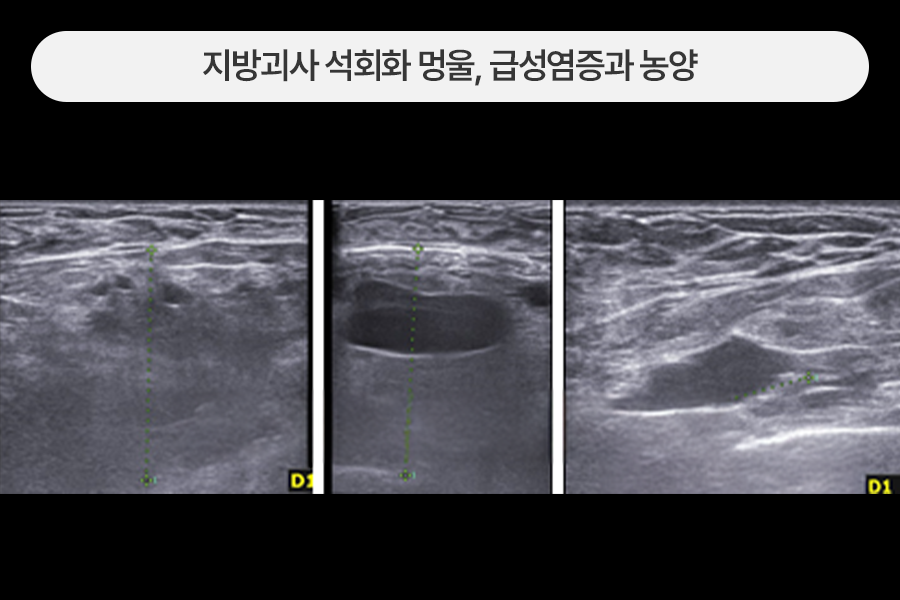

유방 내에 가득 고인 농양 제거

가슴지방이식 후 급성염증이 심하게 생긴 분으로 유방 내부에 큰 농양(고름집)이 형성된 상태였습니다.

이런 경우는 보통의 지방이식부작용 치료에 비해 절개가 커지고 1~2주 정도 배액관 거치가 필요할 수 있습니다.